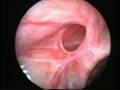

Can this operation be done laparoscopically?

Operation in hydrocele involves closing of the open passage through which the testis has come down. This can be done from outside as in open surgery or from inside by laparoscopy. With the help of laparoscopy we are able to look at the opposite side to see if the passage is open on that side as well. This can be closed at the same sitting if you wish to. Recovery from surgery, timing of surgery and discharge from hospital are the similar for open surgery and laparoscopic surgery.

However, it is important to note that an open passage does not always mean that your child will get a hydrocele or hernia on the opposite side. There is no harm in opting for a second surgery later if your child at all develops a hernia on the opposite side.

Laparoscopic repairs have a slightly higher chance of recurrence as compared to open surgery. You can discuss the pros and cons in details with your doctor when you come for consultation.